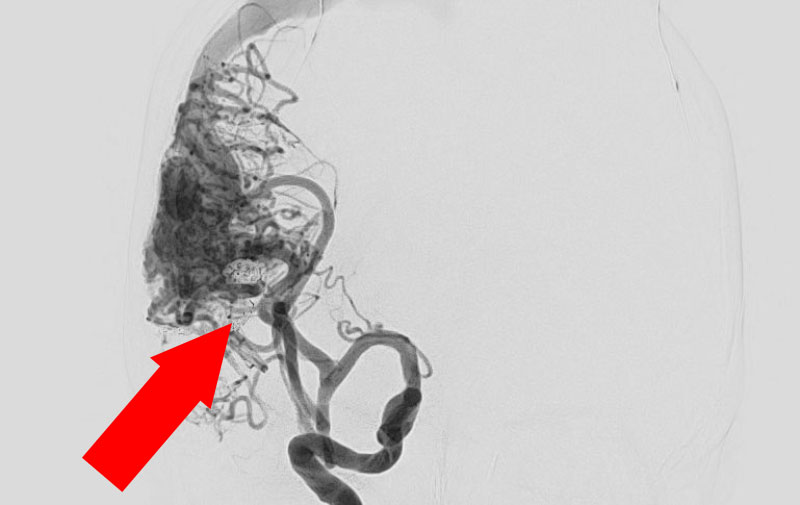

No.1585 手術前

No.1585 手術中

No.1585 手術後